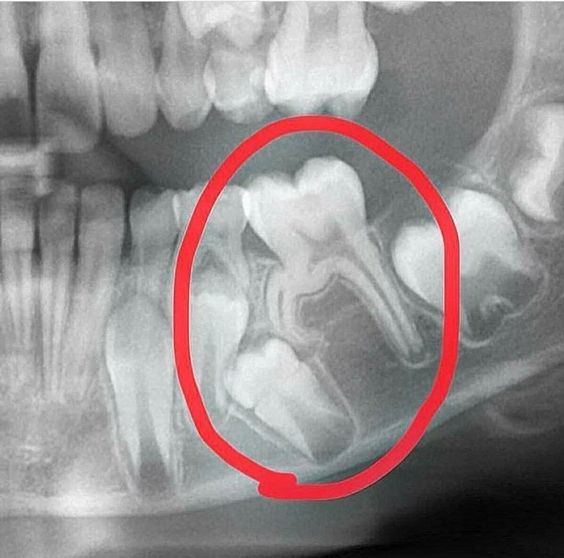

عکس گرافی دندان فک جوش

نتیجه این اختلالات، آمیختگی ریشه دندان با استخوان اطراف است و از حرکت بیشتر دندان در مسیر رویش خود جلوگیری می کند. این عارضه می تواند نه تنها بر روی تراز دندان آسیب دیده بلکه بر روی دندان های مجاور و سلامت کلی دهان نیز تاثیر بگذارد. دندان های انکیلوز شده بیشتر با دندان عقل (مولر سوم) مرتبط هستند و می توانند منجر به عوارض مختلفی از جمله نهفتگی، ناهماهنگی و چالش در حین کشیدن دندان فک جوش و یا دندان عقل فک جوش شوند. تشخیص دندان فک جوش اغلب شامل ارزیابی بالینی و رادیوگرافی کامل برای ارزیابی درجه آنکیلوز و برنامه ریزی استراتژی های درمانی مناسب است.

برای این مطالعه در خصوص دندان های فک جوش و دندان عقل فک جوش، در یک تحقیق دربخش دندانپزشکی کودکان UMFST ، با بررسی عکس رادیوگرافی پانوراما به منظور شناسایی موارد دارای آنکیلوز دندان، جابجایی دندانهای مجاور، ظاهر ناحیه ریشه و ارتباط با بافت استخوانی مورد بررسی قرار گرفت. تحقیقات ارتباط بین آنکیلوز دندان و عوامل جمعیت شناختی مانند جنسیت و سن را مورد بررسی قرار داده است. یافتهها نشان داد که هیچ ارتباط مثبتی بین آنکیلوز دندانی و جنسیت وجود ندارد، اما برخی از مطالعات شیوع کمی بالاتر را در مردان نشان می دهد.اما ارتباط قوی با محل رویش روی قوسهای دندانی مشاهده شد. و نشان داده شده است، دندان فک جوش در فک پایین شیوع بیشتری خواهد داشت.

تشخیص آنکیلوز دندان از طریق ترکیبی از معاینه بالینی و تکنیک های تصویربرداری پیشرفته تشخیص داده می شود. در طول ارزیابی بالینی، متخصصین دندانپزشکی قوس دندانی بیمار را بازرسی می کنند و موقعیت، تحرک و تراز دندان را ارزیابی می کنند. با این حال، مشخصه آنکیلوزدندان عدم تحرک طبیعی آن است. برای تایید تشخیص و ارزیابی میزان آنکیلوز، از ابزارهای تصویربرداری پیشرفته مانند توموگرافی کامپیوتری با پرتو مخروطی (CBCT) استفاده میشود. عکس CBCT تصاویر سه بعدی از دندان ها و ساختارهای اطراف را ارائه می دهد و رابطه پیچیده بین دندان انکیلوز و استخوان مجاور دندان را آشکار می کند. این تصاویر دقیق به تعیین شدت آنکیلوز کمک می کند، که برای برنامه ریزی استراتژی های درمانی مناسب حیاتی است.